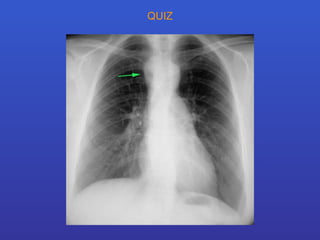

QUIZ